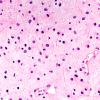

NEOPLASMS (GLIAL)

Astrocytoma, IDH-mutant, WHO Grade 2 (8)